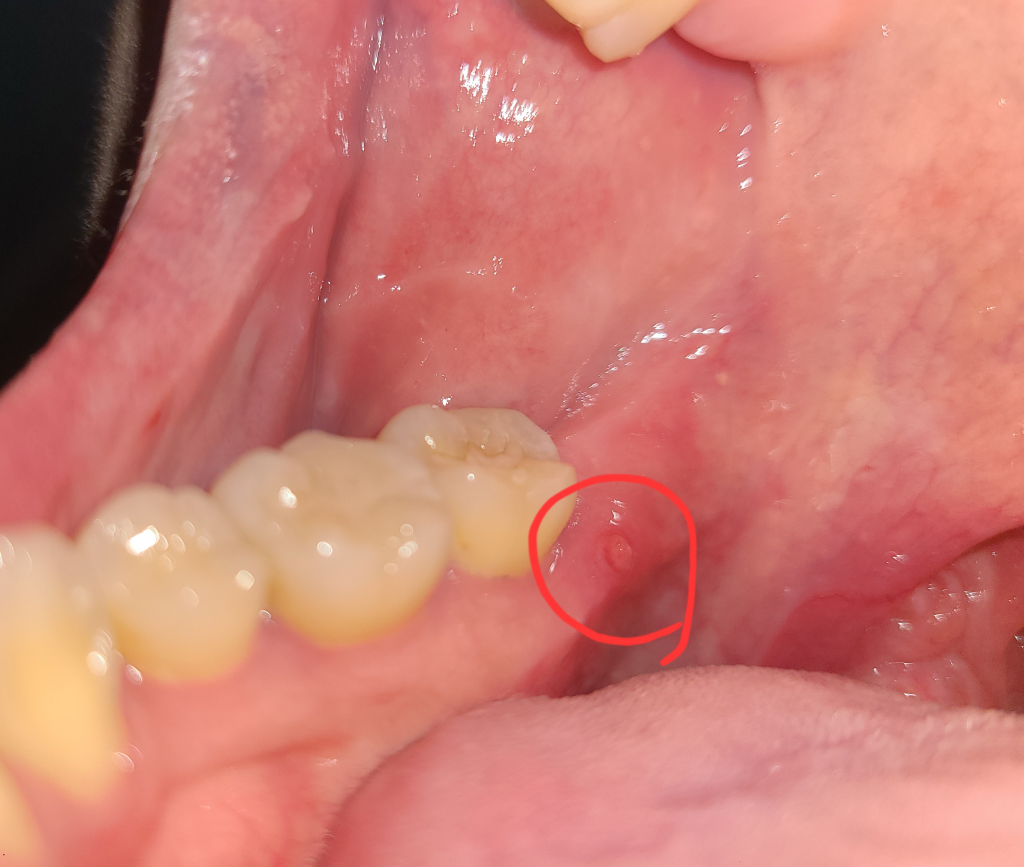

단순 잇몸 염증이라면 치과에 가셔서 마취후에 제거하시면되지만, 뿌리끝에서 나오는 염증이라면 신경치료를 하셔야될수도 있습니다.

안녕하세요. 최석민 치과의사입니다.

사진상으론 점액유출현상 또는 점액류(mucocele)가 의심됩니다. 주로 작은 타액선 배설관에 가해진 외상에 의해 발생하게 됩니다. 치료는 병소의 외과적인 절제입니다. 구강내과가 진료과로 있는 치과에 가서 정확한 진단을 받아보시기 바랍니다. 상기 말씀드린 내용은 사진만 보고 내린 잠정진단이며 정확하지 않을 수도 있습니다.